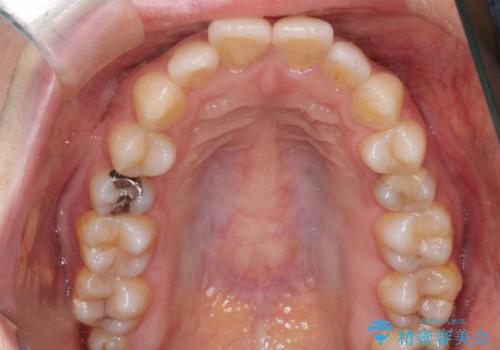

- 「歯のデコボコと前歯が出ているせいで口が閉じにくい」を主訴に来院された患者様です。

上下左右の4番(第一小臼歯)を抜歯をし審美ワイヤー装置で治療を行いました。